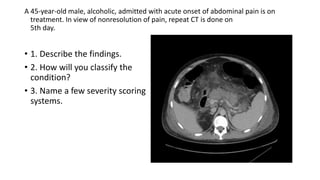

A 45-year-old male, alcoholic, admitted with acute onset of abdominal pain is on

treatment. In view of nonresolution of pain, repeat CT is done on

5th day.

• 1. Describe the findings.

• 2. How will you classify the

condition?

• 3. Name a few severity scoring

systems.